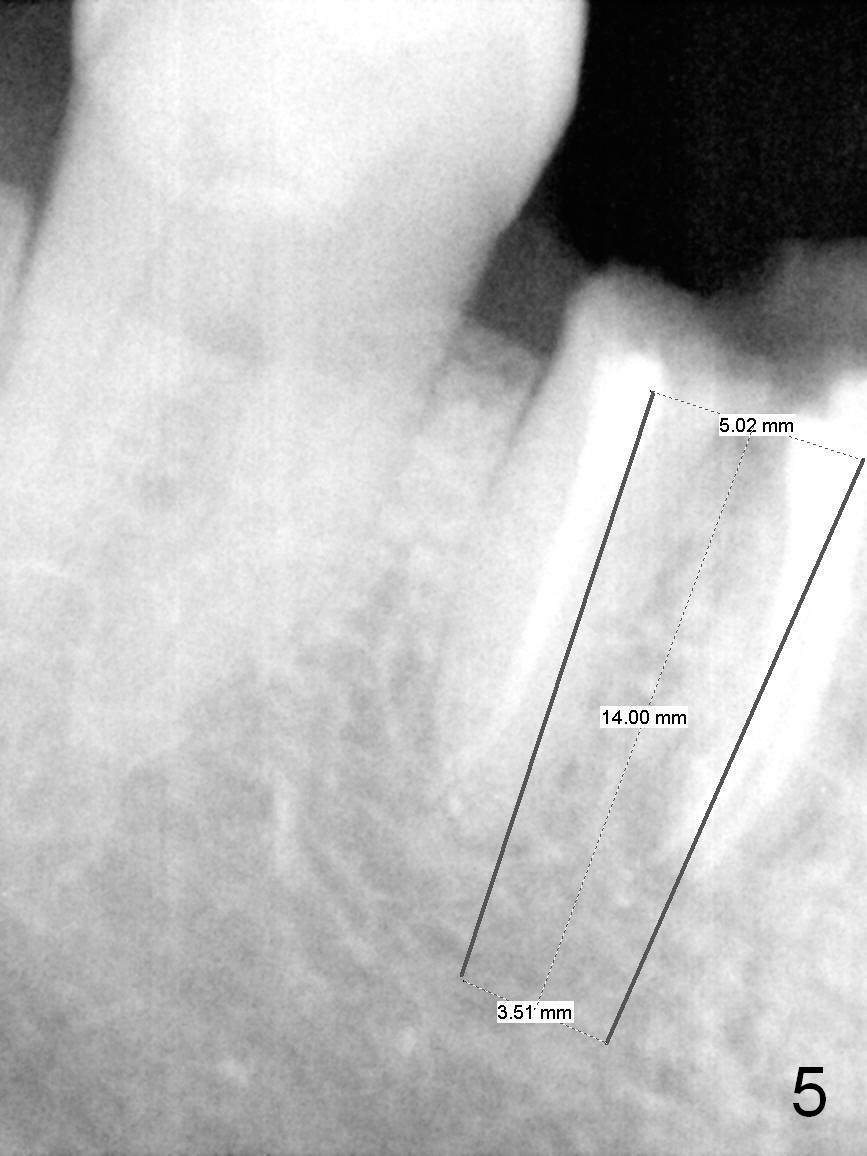

A 68-year-old lady (WQ) had CT taken 3 years ago (Fig.1-3), which show 3 roots (M: mesial; DB: distobuccal; DL: distolingual) of the lower right 1st molar and large caries (C). Recently the tooth fractures after root canal therapy (Fig.4-6).

An implant placed the tripod septum should be stable. The length of the initial osteotomy is 12 mm using 2 mm pilot drill. Take intraop PA as early as possible for trajectory and depth determination.